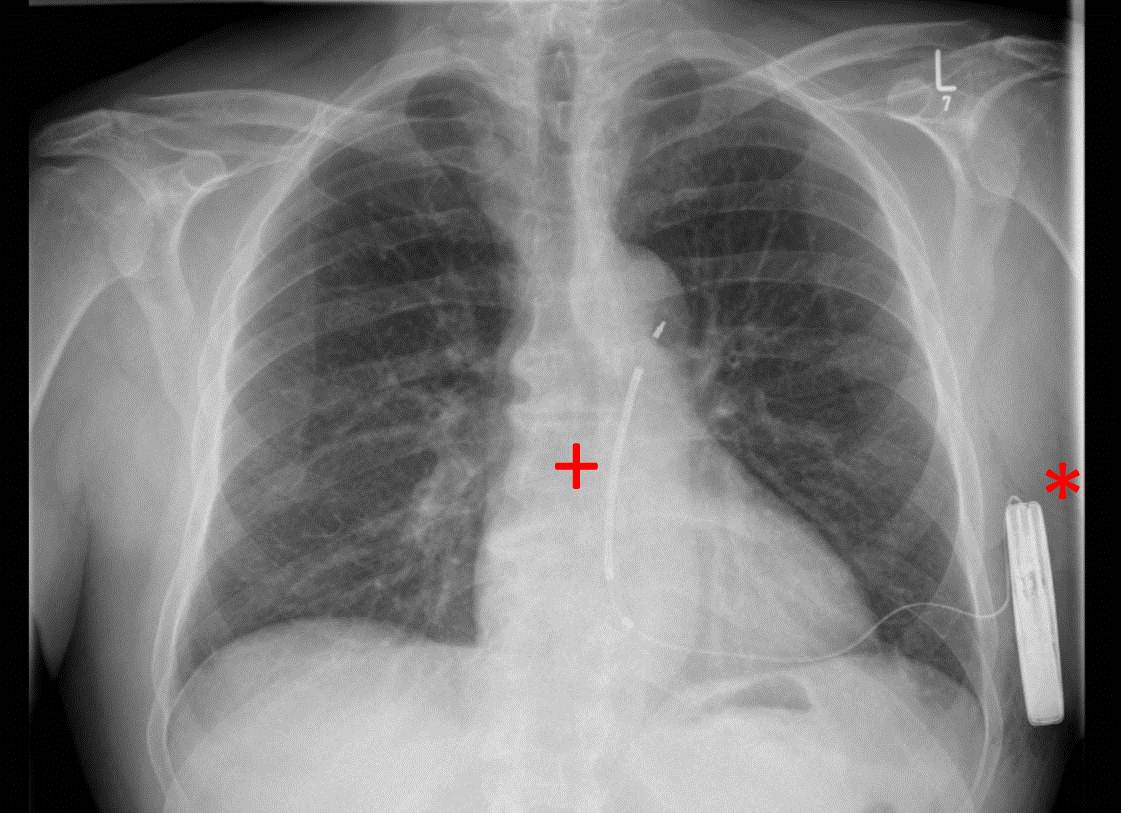

Seit dem Jahr 2009 steht mit den so genannten subkutanen Defibrillatoren ein neuer technologischer Ansatz zur Verfügung: die Aggregate werden auf der linken Seite des Brustkorbes implantiert, die Elektrode verläuft dabei nur noch unter der Haut vor dem Herzen. Seit Februar 2015 ist die zweite Generation dieser Defi-Variante verfügbar und jetzt weltweit erstmals im Herzzentrum Leipzig eingesetzt worden. Das Gerät ist rund 20 Prozent flacher und weist im Vergleich zu seinem Vorgänger eine um 40 Prozent längere Batterielaufzeit auf.

Die Implantation wurde von den Oberärzten Dr. Michael Döring und Dr. Sergio Richter aus der Abteilung für Rhythmologie durchgeführt. Der minimal-invasive Eingriff erfolgte in Narkose, verlief völlig komplikationslos und dauerte nur 30 Minuten. Bereits am Folgetag konnte der Patient aus der Klinik entlassen werden und wird nun ambulant weiterbehandelt.